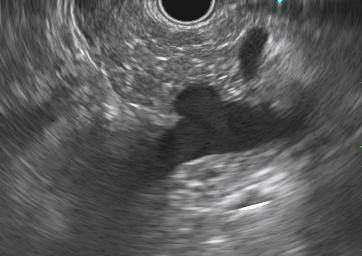

El diagnóstico mediante EUS se basó en la presencia de imágenes pancreáticas hiperecoicas difusas o discontinuas, con bordes poco definidos y dificultad para caracterizar el conducto pancreático principal, en lugar del aspecto habitual bien definido de «sal y pimienta» (véanse las imágenes ilustrativas en el artículo).

Imágenes ilustrativas: